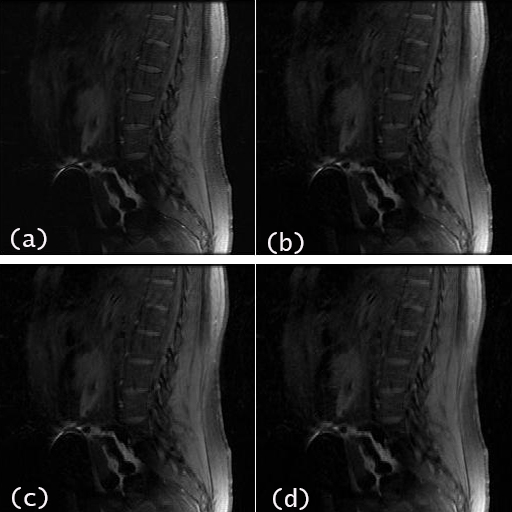

The proposed convex optimization method is applied to two sets of in-vivo MR data for reconstruction and performance evaluation. The first brain data set was acquired on a 3T scanner (GE Healthcare, Waukesha, WI) using an -channel head channel (Invivo, Gainesville, FL) and a 2D -weighted spin echo protocol with axial plane, ms, FOV=, slices and matrix size. The second spine data set was acquired using an -channel cervical-thoracic-lumbar spine array and a fast spoiled gradient-echo sequence with ms, RBW kHz, , Tip angle and FOV = . The fully sampled -space data sets were in the cartesian coordinate system and were manually undersampled by uniform sampling with additional auto-calibration signal (USACS) lines in the phase encoding direction.

For the spine data set, the reconstructed image by SOS is given in Fig.5 (a) followed by that reconstructed using the proposed method Fig. 5 (b), for nominal undersampling rate . The NMSE of this reconstructed image is . For higher reduction rates of and , the corresponding reconstructed images by the proposed algorithm are shown in Fig.5 (c) and 5 (d) with NMSE values and , respectively.